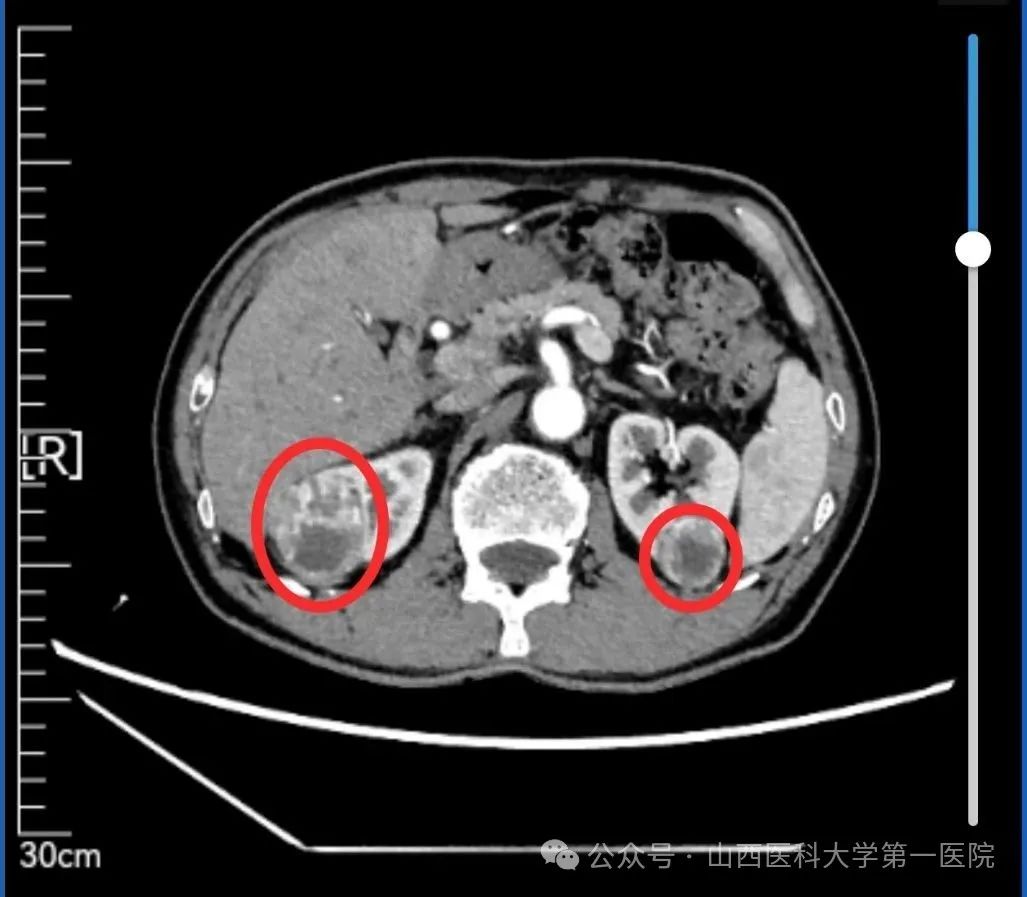

术前CT影像可见双侧肾肿瘤病灶,红色圈内即为肿瘤病灶

术前CT报告提示双侧肾癌